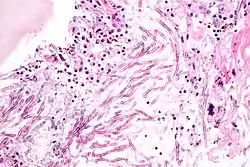

![]() صورة مجهرية تظهر ذات الرئة الفطري (داء الرشاشيات الرئوي). صبغة H&E. صورة مجهرية تظهر ذات الرئة الفطري (داء الرشاشيات الرئوي). صبغة H&E. | |